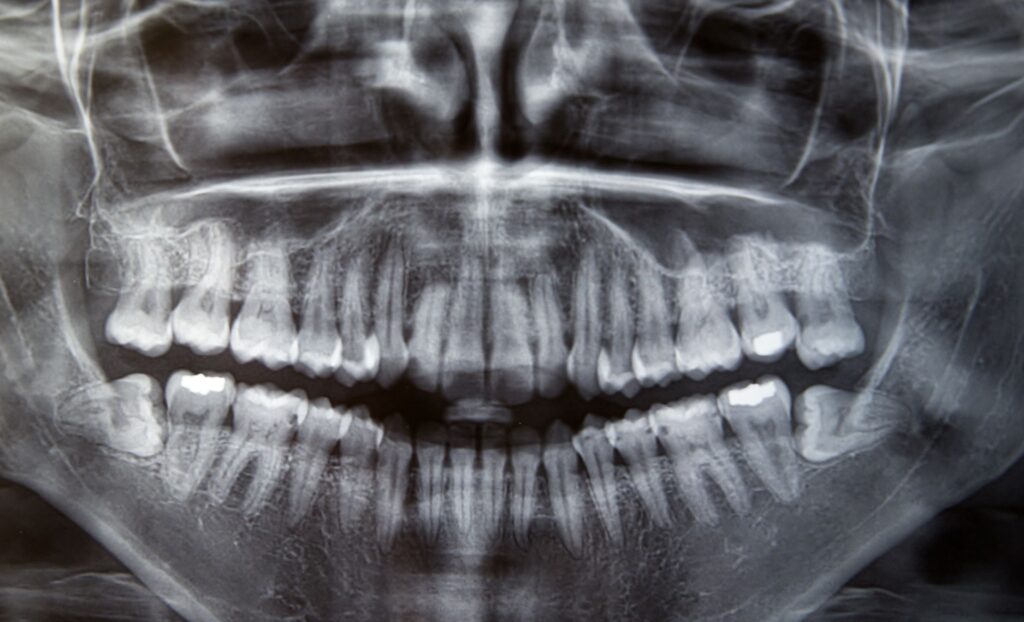

El hueso alveolar es como conocemos a la estructura ósea sobre la que se integran las raíces dentales. Junto con los tejidos gingivales mantienen a la pieza dental en su sitio y aseguran su estabilidad. Sin embargo, son varios los motivos que pueden propiciar un desgaste en este hueso, que al principio es muy difícil […]